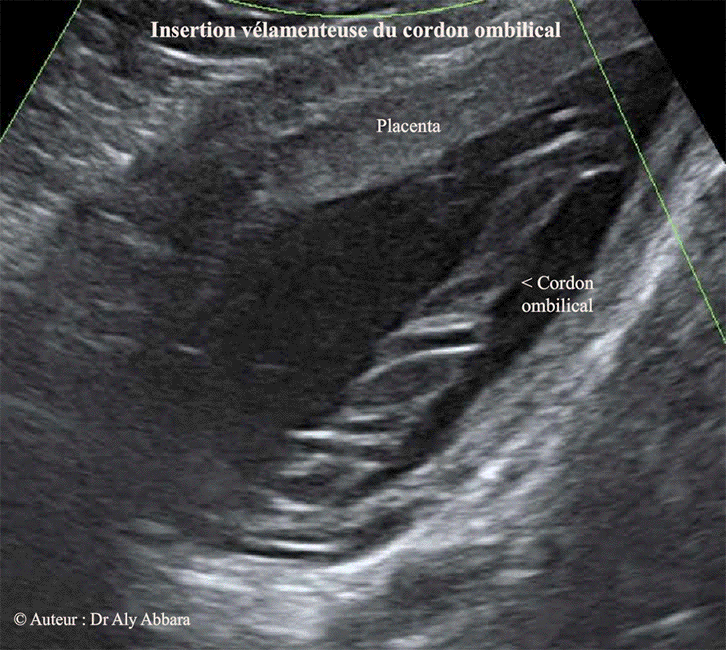

| Images échographiques montrant une insertion vélamenteuse du cordon ombilical : le cordon s'insère d'abord sur les membranes amniotiques, puis ses vaisseaux sanguin parcourent ces membranes sur une distance plus ou moins longue avant d'atteindre le bord placentaire Fœtus âgé de 26 SA |